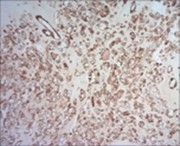

Figure 4.Parachordoma depicting cords and aggregates of vacuolated cells with acidophilic cytoplasm and regular, miniature nuclei with an encompassing myxoid stroma 15.

Figure 5.Parachordoma exhibiting nests and clusters of spheroidal cells with eosinophilic, vacuolated cytoplasm, uniform, bland nuclei and a circumscribing myxoid stroma 15.